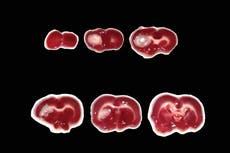

Los hallazgos son significativos dado que la probabilidad de que un tumor de mama migre o haga metástasis a otras partes del cuerpo aumenta en más de un tercio en las personas menores de 35 años.